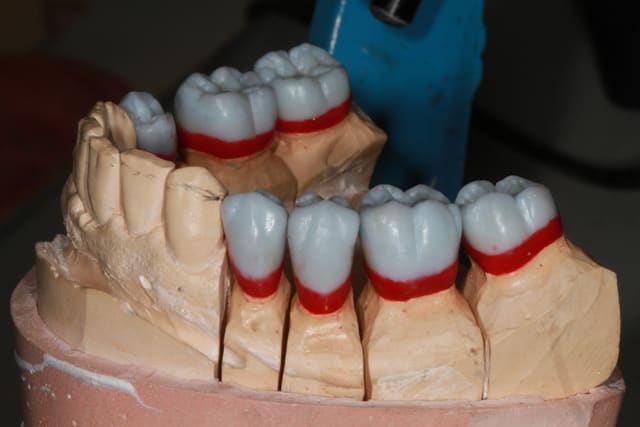

25/09/2013 à 22h10

Wax up et taille crayon...

Empreinte, détourage et préparation des cires avec une occlusion différente de celle du wax up, un peu plus de DV